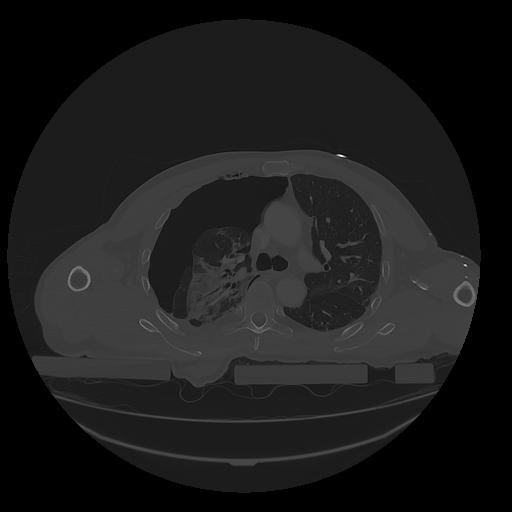

31 PULMON,CE,Vol,1.0,PULMON,,